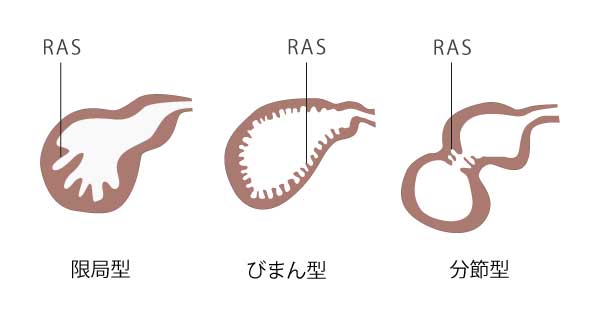

腺筋腫症にはいくつかの異なるタイプがあります。

- 局所:局所腺筋腫症は、

最も一般的な タイプ。これには、1 つの部位、通常は胆嚢の最も広い部分である底部が肥厚することが含まれます。子宮底腺筋腫症とも呼ばれます。 - 環状:環状腺筋腫症には、胆嚢の周囲で肥厚する組織領域が含まれます。これにより、胆嚢の内部が砂時計のような形状になります。

- 分節性:分節性腺筋腫症は、組織のより広い領域が肥厚し、通常は眼底を超えて広がります。胆嚢の患部は内側に収縮しますが、残りの組織は正常に見えます。

- びまん性:びまん性腺筋腫症は胆嚢全体に影響を与えます。